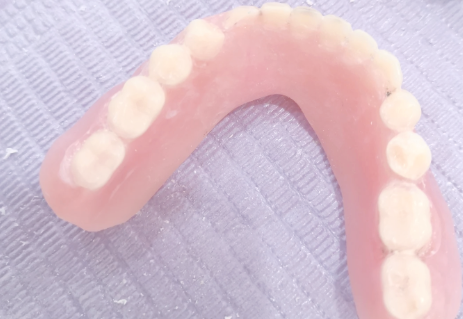

活动义齿一般多少钱一颗费用?2026年最新价格揭秘! 文章揭秘2026年活动义齿最新价格。通常镶活动假牙一颗1000 - 3000元,不同类型费用有别。如隐形义齿1000 - 1200元,便宜但寿命短、咀嚼差;钴铬合金等1500 - 2000元,强度好、使用久;纯钛基托2000 - 3000元,舒适美观。此外,地区、医院等级和医生水平也影响价格,选义齿要综合考量。 活动义齿 2026年03月04日 0 点赞 0 评论 7 浏览

活动义齿哪种最舒服还不伤害基牙?揭秘3种最佳选择! 本文围绕“活动义齿哪种最舒服还不伤害基牙”展开。首先强调了活动义齿舒适与护基牙的重要性,接着介绍了纯钛金属基托活动义齿等三种义齿的特点,包括舒适度、对基牙的影响、价格等。还给出选择建议,要考虑口腔状况、经济因素,并听取医生建议。最后提醒佩戴后注意适应期、清洁和饮食,综合考量选适合自己的义齿。 活动义齿 2026年03月04日 0 点赞 0 评论 12 浏览

补一颗活动义齿多少钱?揭秘真实费用与选择技巧! 本文围绕补一颗活动义齿的费用及选择技巧展开。费用大致在100 - 300元,受材料、修复难易、医院级别、当地经济等因素影响。不同材料义齿各有特点和价格区间。选择时要综合自身情况,选正规机构,多对比。此外,后期维护有成本,需正确佩戴清洁。提醒大家综合考量价格、质量和舒适度,必要时咨询医生。 活动义齿 2026年03月04日 0 点赞 0 评论 7 浏览